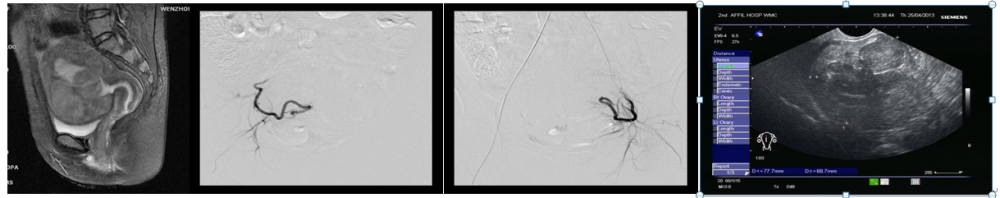

案例7: 陈**,女,37岁,经期延长、经量增多1年,MRI提示多发子宫肌瘤,最大者约6*7*6cm,患者要求介入治疗,行双侧子宫动脉栓塞术,术后3月复查:症状完全缓解,子宫肌瘤体积缩小;6个月后复查:意外怀孕,B超提示早孕,胚胎存活。